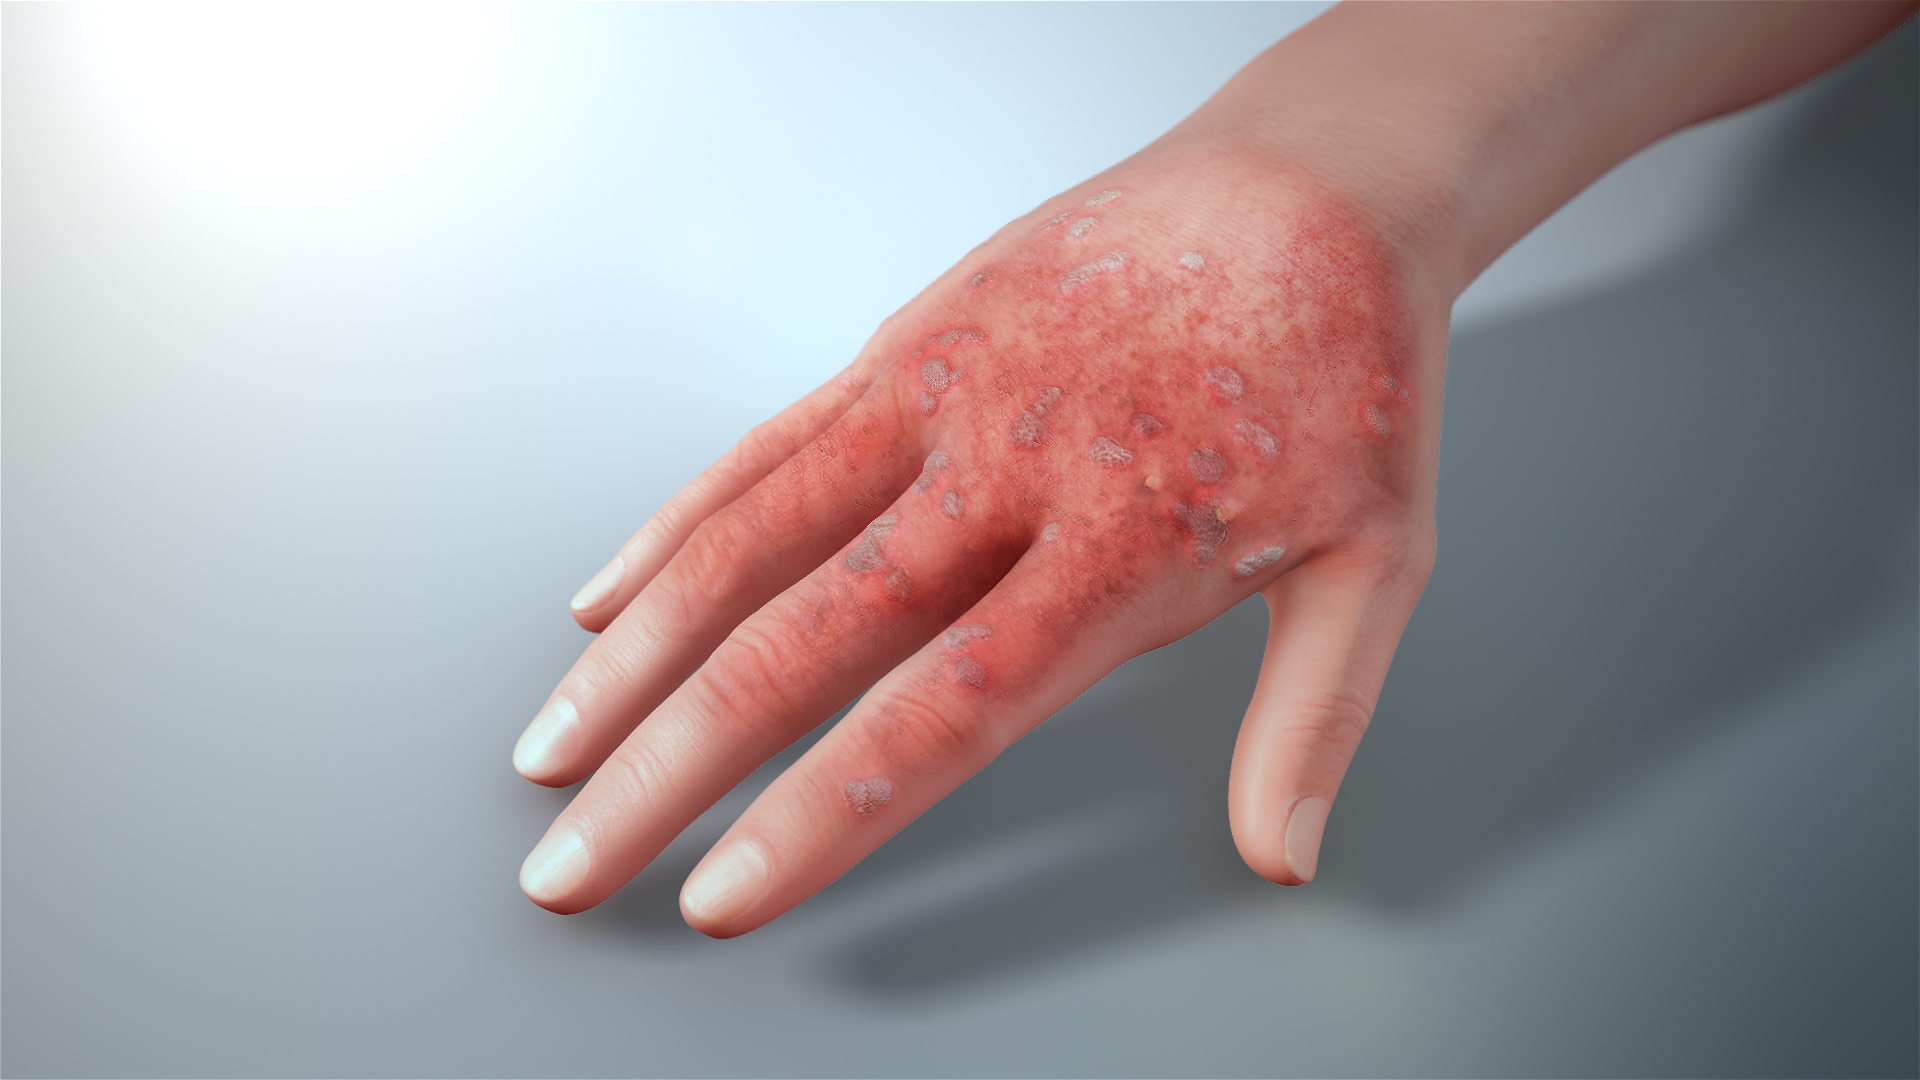

Симптомы кондилом могут варьироваться, и визуальное представление этого заболевания может быть различным. Некоторые кондиломы выглядят как небольшие бугорки или бородавки, в то время как другие могут иметь форму плоских пятен или цветных наростов.